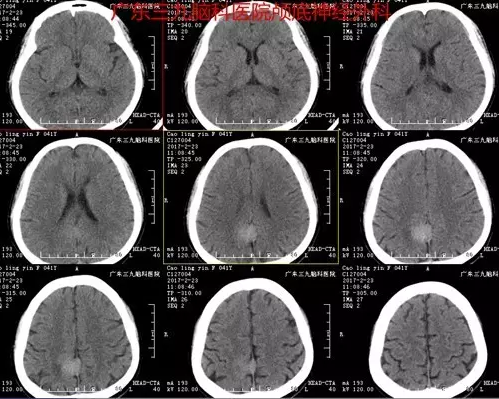

曹某,女性,41岁,因“头痛1月余”前来就诊。入院后完善相关检查,磁共振检查结果提示右侧额顶叶占位性病变,行“右侧大脑镰旁脑膜瘤切除术”,手术顺利,术后磁共振提示肿瘤切除。术后诊断:右侧大脑镰旁脑膜瘤。

图1:CT示右侧大脑镰旁类圆形稍高密度影

据神经外一科刘振业主任介绍,大脑镰旁脑膜瘤是指基底附着于大脑镰或上矢状窦窦腔脑膜瘤,约占颅内脑膜瘤的11%-13%。手术治疗是大脑镰旁脑膜瘤的首选治疗方式。然而,由于镰旁脑膜瘤常常隐藏于大脑皮质下方,并且缺乏早期神经系统症状,导致早期诊断较为困难,一经发现往往肿瘤体积已形成占位效应,并引起如头痛、肢体麻木等神经症状。本例患者为中年女性,以头痛为首发症状,CT示小团状稍高密度影,边界欠清晰,密度尚均匀,血供丰富,MR见病变明显强化,脑膜尾征明显,邻近组织少许片状水肿。